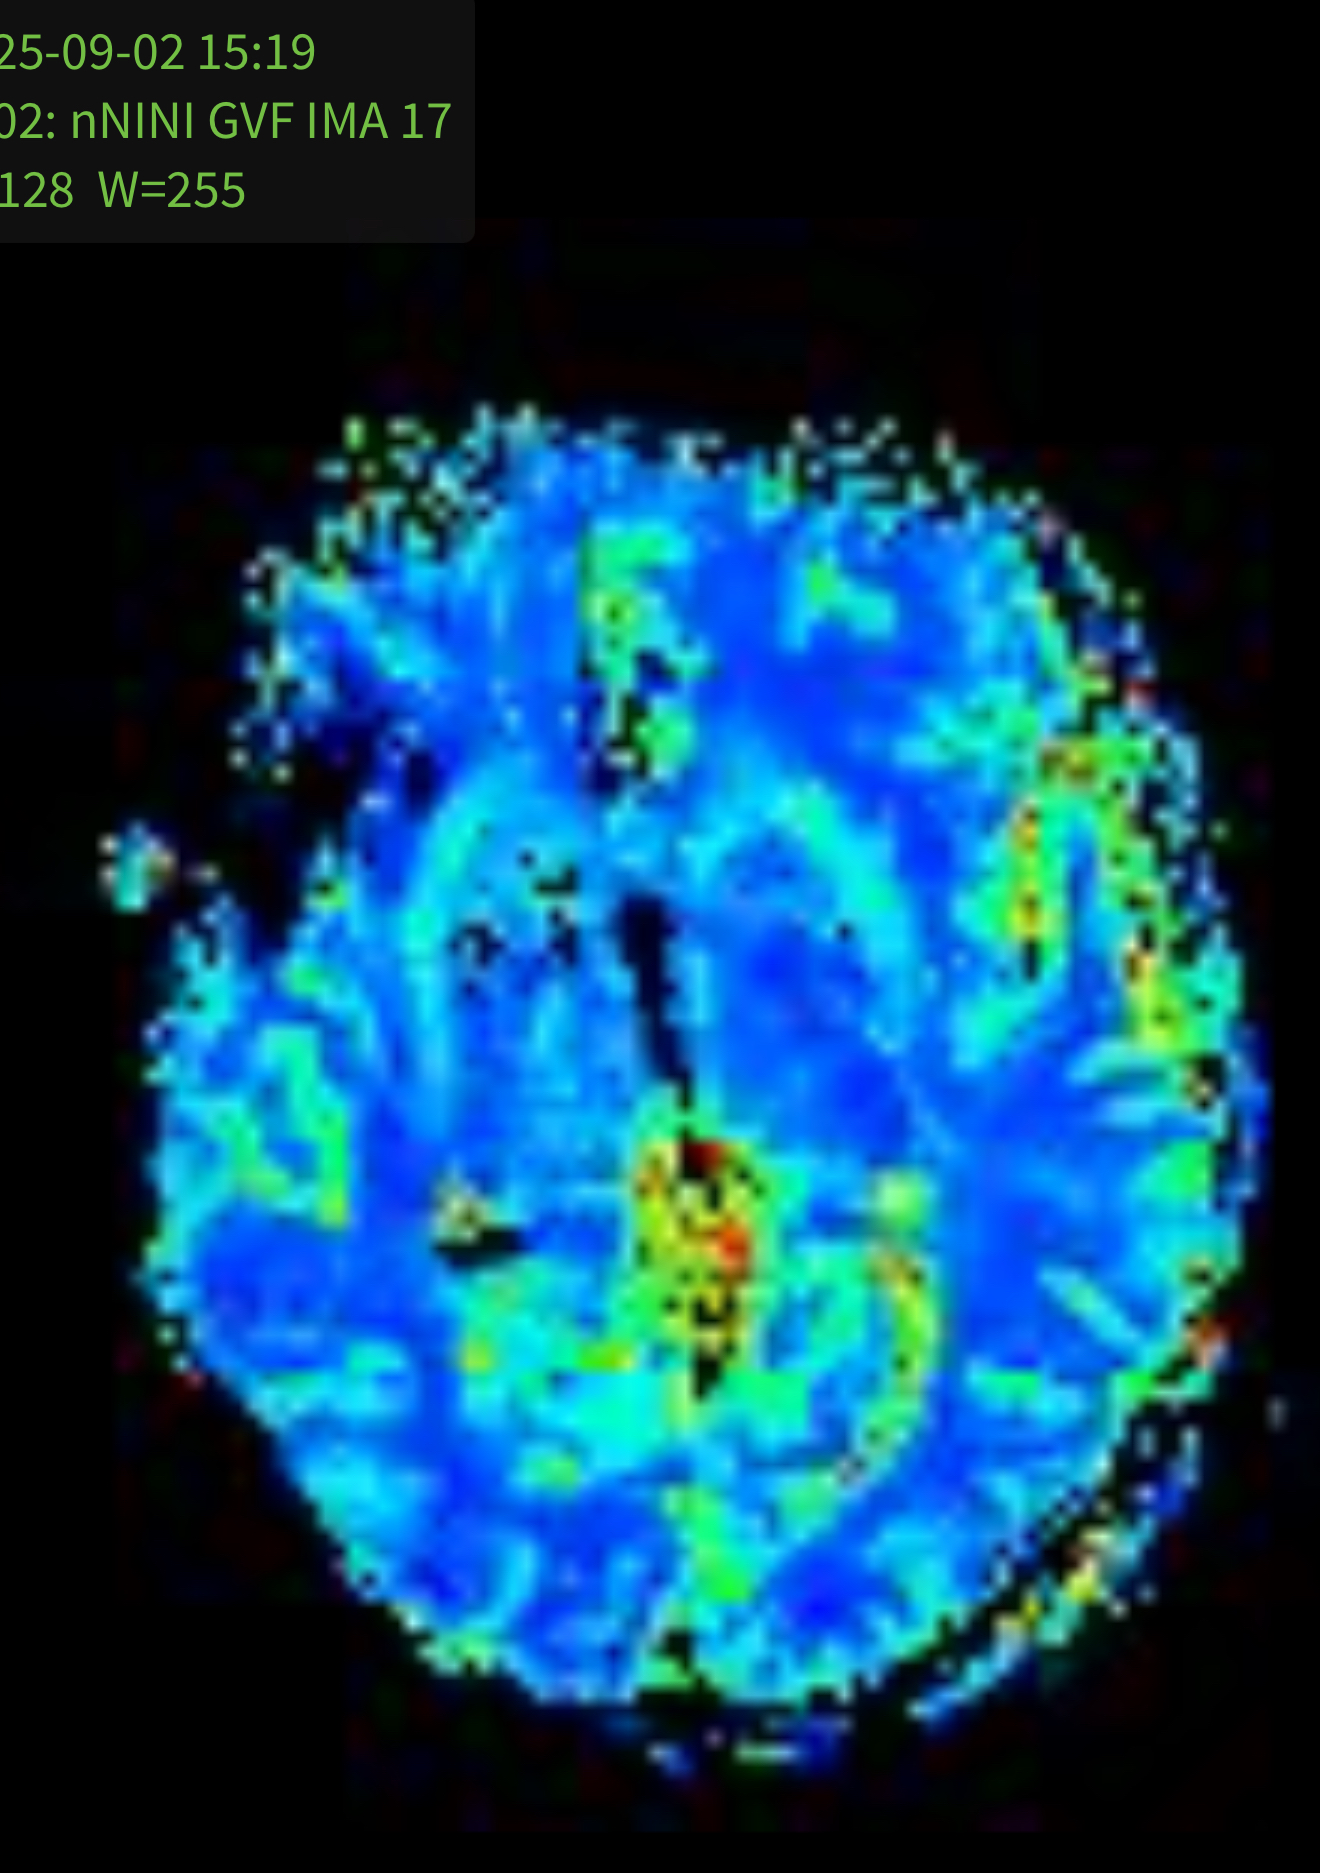

Based on that information, he ordered a new scan for one month later with some additional “advanced imaging” called “MR Perfusions”. This scan, which takes an additional 15 minutes while laying still in the MRI machine, looks deeply into the blood flow patterns of the brain. This is an important scan, since a cancerous tumor requires a lot of blood and will show new vein growth in the affected area. So, if the new MRI would show rapidly increased size AND new blood vessel growth, this would be a strong indication of a new tumor.

This leads us to today. We got a new MRI on September 2nd (2 days ago) and visited the doctor this morning. He showed us the images of the new MRI which did show a slight increase in the size of the affected area, but no new blood vessel growth in the new scan.

In the first image, you can see the spot on the left side of the image (right side of the brain since the images are reversed), but on the second image, you can see the area where the spot is does NOT show any highlights or additional blood flow.